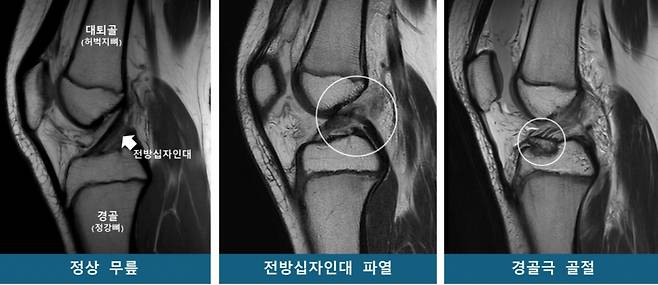

연구팀은 소아청소년을 53명씩 ▲전방십자인대 파열군 ▲경골극 골절군 ▲대조군(정상 무릎)으로 구분하고 연령·성별을 매칭했다. 이후 MRI를 재구성한 3차원 영상을 바탕으로 14개의 해부학적 지표를 분석했다.

그 결과, 두 무릎 손상군은 대조군보다 '경골 바깥쪽 관절면 경사'가 유의미하게 높았다. 통계 분석에 따르면 경사가 높을수록 전방십자인대 파열 및 경골극 골절 발생 위험이 각각 1.42배, 1.33배 증가해, 이 값이 소아청소년의 주요 무릎 손상에 대한 위험인자로 확인됐다.

반면, '무릎뼈 사이 공간(대퇴과간 절흔 폭)'은 전방십자인대 파열군에서만 유의미한 연관성이 있었다. 특히 이 폭이 넓을수록 파열 위험이 감소하는 보호 효과가 확인됐다.

연구팀은 "경골(정강뼈) 바깥쪽 관절면의 경사가 가파를수록 무릎에 무게가 실릴 때 대퇴골(허벅지뼈)이 바깥으로 회전하며, 그 결과 전방십자인대가 과부하돼 파열, 경골극 골절로 이어질 수 있다"고 설명했다. 또한 무릎뼈 사이 공간이 넓으면 전방십자인대가 대퇴골과 덜 충돌하기 때문에 파열 위험이 낮아지는 경향이 있다고 밝혔다.